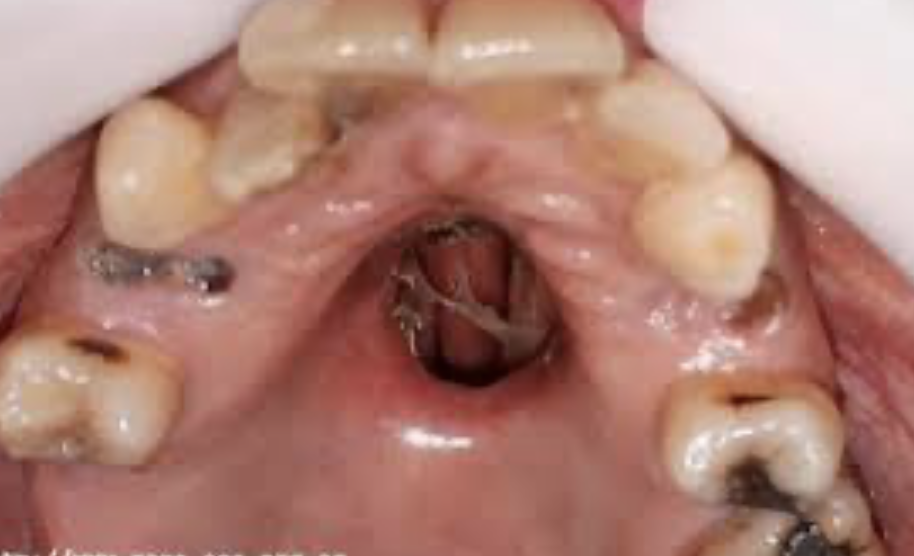

¿Cuál es la complicación más común post-extracción de molares superiores relacionada con el seno maxilar?

Comunicación oro-antral: conexión entre la cavidad oral y el seno maxilar, que puede causar sinusitis (infección) si no se cierra adecuadamente.

35

Dx

Comunicación oro-antral